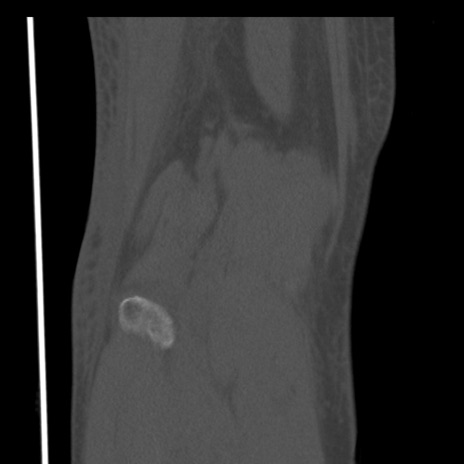

右膝関節CT

矢状断像